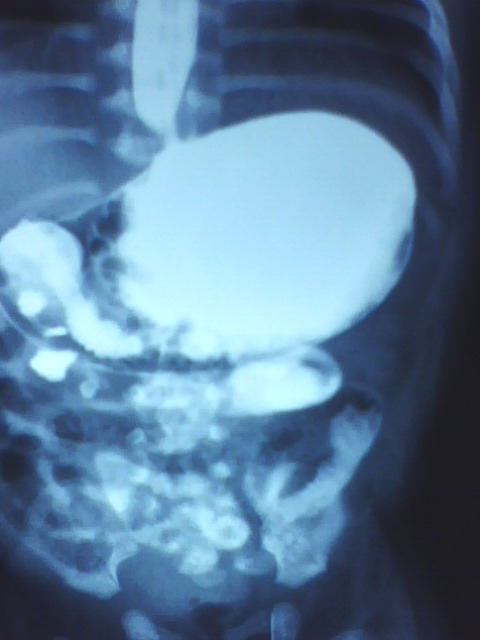

以下是引用拾荒者在2009-10-14 20:41:00的发言:[br]要查的话也应该做钡灌肠,看有否巨结肠及乙状结肠冗长症等;做上消化道钡餐想看什么?5天的小儿肠腔胀气是正常的。